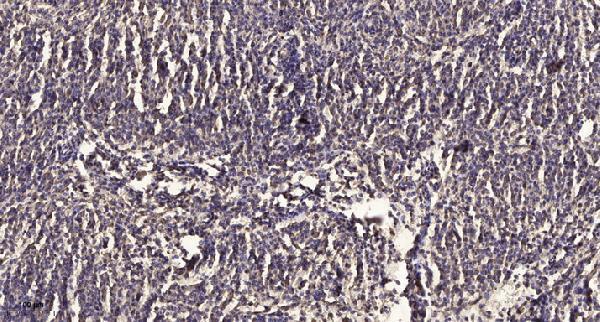

Sodium/potassium-transporting ATPase subunit alpha-2